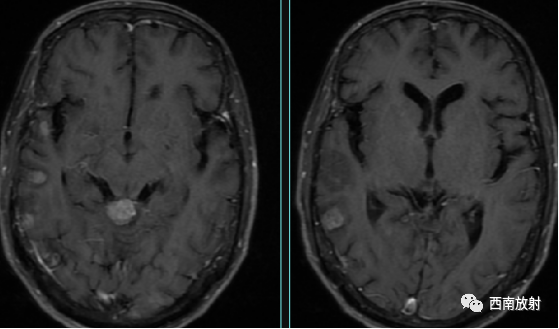

4.感染性病变:发病年龄相对年轻,部分有发热病史。增强扫描时,细菌性感染病变多出现环状强化,多发性硬化多出现斑块状强化。近年来由HIV感染引起的免疫功能低下型淋巴瘤增多,病灶常多发,环状强化多见,肿瘤中心坏死多见。临床症状严重,发病凶险,病情进展快,病死率高,可通过实验室检查,治疗及临床症状的发展来鉴别;

▲图 脑出血,治疗后期,脑压增高,脑积水,颅内感染性病变。增强扫描显示多灶性及多发环状强化。